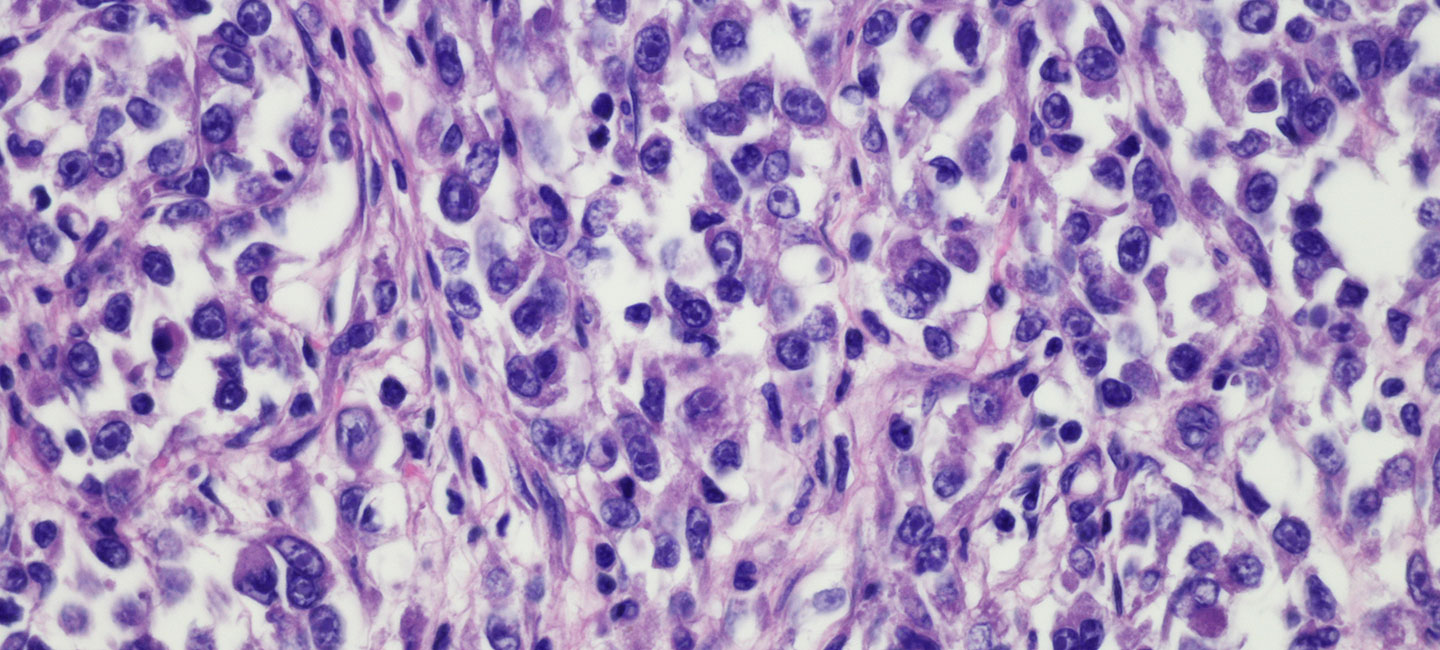

Considered to be among the great advances in oncology over recent years, tumor infiltrating lymphocyte (TIL) therapy and adoptive cell therapy (ACT) is a specific immunotherapy strategy that uses T cells to treat cancer. Patients receive an infusion that effectively “swaps” their peripheral, circulating T cells with those that are grown from a patient’s own tumor and thus tumor-responsive. While these treatments have been effective for treating metastatic melanoma and other hematologic tumors, the Sarcoma Oncology Program at Moffitt Cancer Center has developed a strategy to treat patients with soft tissue sarcoma in the same way.

Moffitt is currently treating adolescent and young adult (AYA) sarcoma patients on an ACT clinical trial and work in the lab is focused on optimizing the strategy further. AYA patients have the lowest clinical trial participation rate of all age groups and slower progress in survival improvement than younger patients, making this opportunity especially unique for patients. Dr. John Mullinax, an assistant member in Moffitt’s Sarcoma Department and the trial’s principal investigator, presented data from his lab at this year’s Society for Immunotherapy of Cancer (SITC) Annual Meeting in Washington, D.C. The results describe specific types of TIL (CD8+CD69+) that have shown increased tumor-specific response in soft tissue sarcoma and therefore represent a strategy to optimize the cell product that patients receive on future trials.